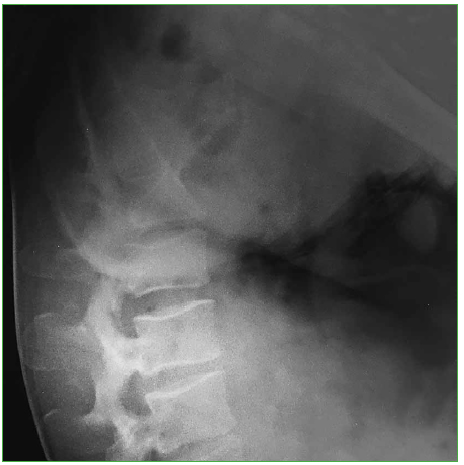

Al ingresar está reactivo y lúcido (escala de Glasgow 15/15), con estabilidad hemodinámica. El examen neurológico revela paresia de ambos miembros inferiores (grado D, según el puntaje de la ASIA). Se toman radiografías, una TC y una resonancia magnética de columna cervical, torácica y lumbar que muestran una fractura de tipo estallido del cuerpo vertebral de L4 con múltiples fragmentos voluminosos del muro posterior que ocupaban el canal medular con subluxación L3-L4. Se interpreta, según la clasificación AO, como C:L3-L4 (L4: A3, N3) (Figuras 9 y 10).

Figura 9.

Caso 2. Radiografía inicial (perfil).

Figura 10.

Caso 2. Tomografía computarizada, corte axial.